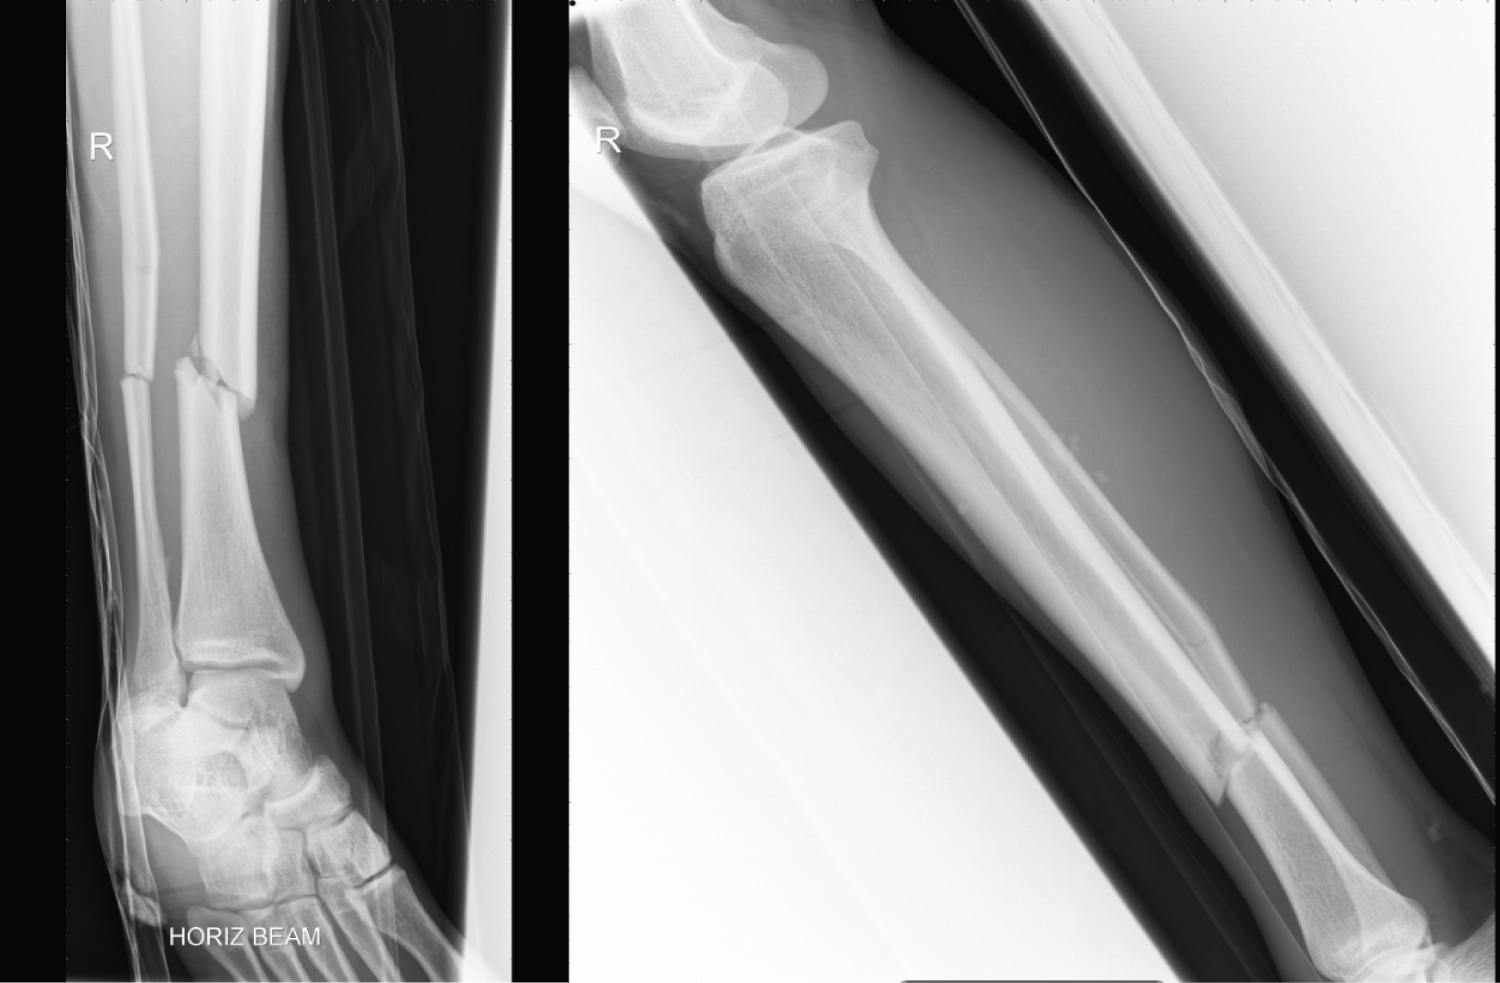

A 20 year old man suffered a closed, oblique fracture of his right tibial diaphysis at the junction of the middle and distal third with an associated fibula fracture whilst playing football (Figure 1). His tibia was stabilised with an antegrade, reamed, intramedullary nail and proximal and distal bolts, on a planned trauma list. The position on intraoperative fluoroscopy and post-operative radiographs show an appropriate reduction and position of the nail (Figure 2). Immediate weight bearing as pain allows was commenced post-operatively and after clinical and radiographic union, was permitted to return to sport and work as a crane driver.

Figure 1: AP + Lateral X-ray prior to surgical intervention. View Figure 1